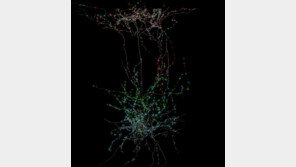

포유류의 뇌 속 구조와 기능의 관계를 종합적으로 밝힌 세계 최대 규모의 데이터셋이 공개됐다. 생쥐 대뇌 시각피질 1mm³를 분석해 뇌세포의 연결망과 실시간 활동, 유전자 정보를 함께 결합한 결과다. 그동안 신경과학 분야에서 규명되지 않았던 ‘억제성 뉴런’의 원리를 새롭게 규명했다. 인…